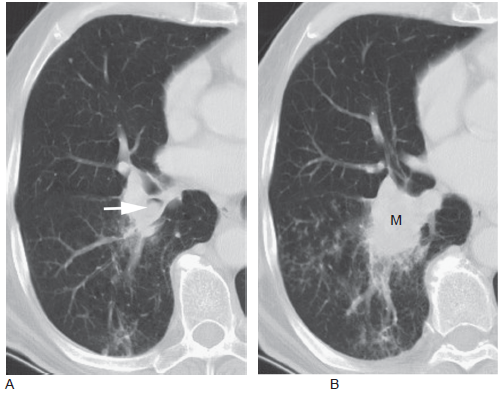

肺门肿瘤

肺门肿瘤,肺部肿瘤

右侧肺门区肿瘤.

肺门的肿块也很常见,这归因于肿瘤位于中心位置,可侵犯局部组织,累及

肺门肿瘤图片

肺门ct